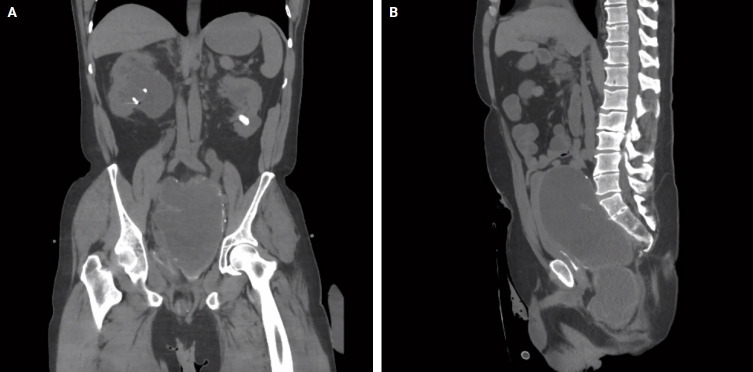

粘液囊肿,常见于阑尾,是由多种病因引起的充满粘液的扩张结构。与发育不良或肿瘤上皮相关的病例可在腹腔内破裂和扩散。结肠其他部位的类似病变极为罕见,仅报道了16例结肠粘液囊肿。首例结肠黏液性肿瘤伴不典型增生,类似低级别阑尾黏液性肿瘤累及直肠残端,于2016年报道。在这里,我们提出的第二个这样的情况下,出现在直肠残端,确定在一个44岁的男性有广泛的手术史。显微镜检查显示,囊肿内有低级别发育不良的上皮,黏液进入间质,未见破裂或外膜黏液。患者随访16个月,无复发或腹膜疾病。这些罕见病变的确切病因和结果尚不清楚,需要密切随访。

Mucoceles, commonly observed in the appendix, are mucin-filled, dilated structures arising from a range of etiologies. Cases associated with dysplastic or neoplastic epithelium can rupture and disseminate within the abdominopelvic cavity. Similar lesions in other parts of the colon are exceedingly rare, with only 16 colonic mucoceles having been reported. The first case of a colonic mucinous neoplasm with dysplasia resembling a low-grade appendiceal mucinous neoplasm involving rectal stump was described in 2016. Here, we present the second such case arising in the rectal stump, identified in a 44-year-old male with extensive surgical history. Microscopic examination revealed low-grade dysplastic epithelium lining the cyst and mucin dissecting into the stroma, without evidence of rupture or extramural mucin. The patient was followed for 16 months without recurrence or peritoneal disease. The exact etiology and outcome of these rare lesions remain unknown, requiring close follow-up.